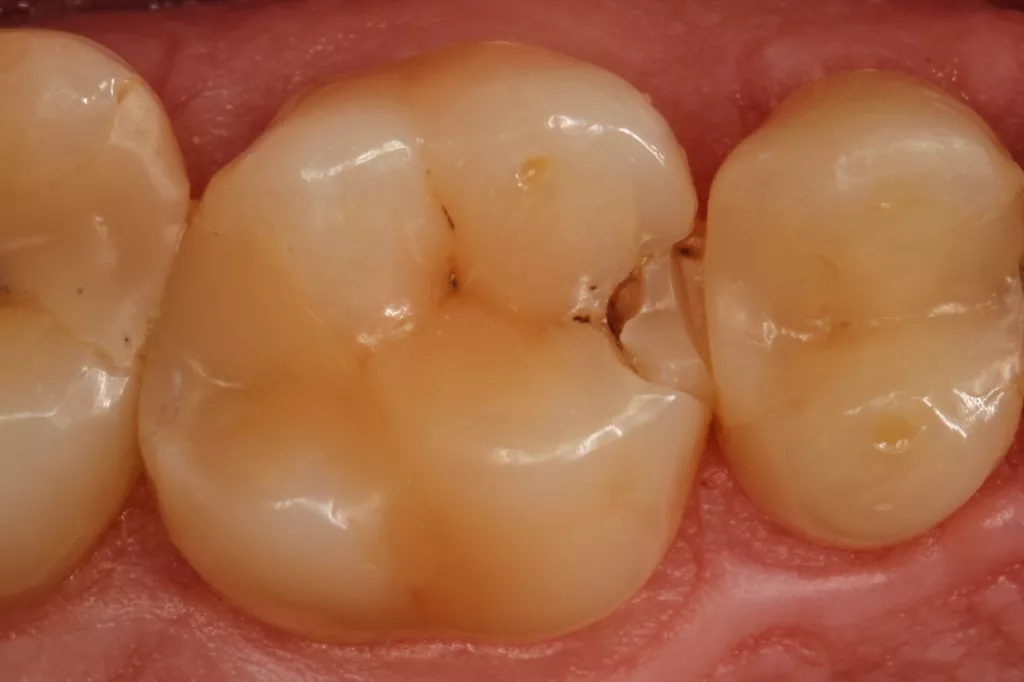

Fall 5: Versorgung einer okklusalen Kavität an einem unteren Molaren

Auch im Molarenbereich können Bulkflow-Materialien effektiv und ökonomisch eingesetzt werden, ohne Abstriche an der Ästhetik machen zu müssen, was der Fall des hier versorgten Zahnes 46 bei einer 22-jährigen Patientin zeigt. Die Abbildung 24 stellt die bereits präparierte und mit einem Einzelzahnkofferdam isolierte Kavität mit der Phosphorsäurekonditionierung der Schmelzränder (Gel Etchant, Kerr) dar. Die Entscheidung zur absoluten Trockenlegung fiel aufgrund der nicht so einfach kontrollierbaren Zunge und der vielen Schluckreflexe, was das Risiko einer ungewollten Speichelkontamination der Klebefläche unverhältnismäßig erhöhte.

Die Verwendung des Kofferdams ist generell eine sehr empfehlenswerte, aber keine zwingende Voraussetzung zur Etablierung einer suffizienten Kontaminationskontrolle [47,96]. Das bisher auch bereits verwendete Zwei-Schritt-Universaladhäsiv G2 Universal wurde hier in der selektiven Schmelzätztechnik angewendet, d.h., das Material arbeitet auf dem Dentin selbstkonditionierend (Abb. 25). Die bislang zu diesem innovativen Mehrflaschen-Universaladhäsiv publizierten Daten zeigen eine beeindruckende Performance, die den Vergleich mit sogenannten Goldstandards [98] wie einem Optibond FL nicht scheuen müssen [13,18,34,58,63,114,119,127,130]. Im nächsten Schritt wurden die einzelnen Höcker mit dem angenehm standfesten Flowable aufgebaut (Abb. 26). Die Abbildung 27 zeigt die komplett versorgte okklusale Kavität, die Abbildung 28 die Situation unmittelbar nach Ausarbeitung und Politur. Erneut beeindruckt die gute Farbadaptation.